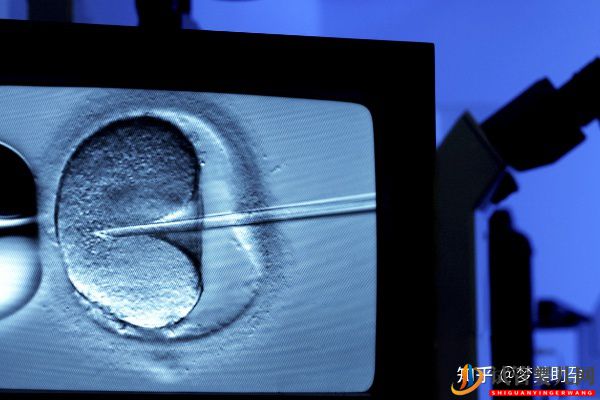

第二代试管婴儿技术ICSI,指借助显微操作系统将单一精子注射入卵子内使其受精,完成精卵结合,形成受精卵。美国生殖医生将会在高倍显微系统下,用非常细的玻璃吸管吸住成熟卵子的一侧,用另一支吸取一条健康的精子,直接将其注射到卵子内,使精子绕过卵子的透明带及质膜,直接受精。